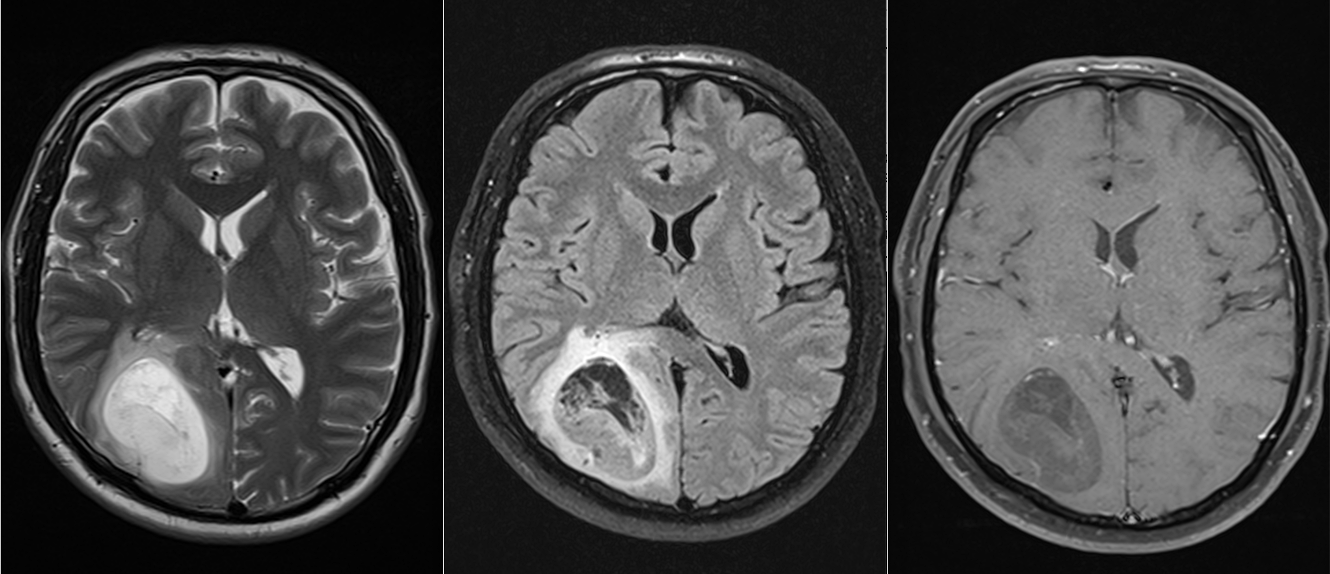

Investigația prin RMN cerebral a clarificat situația: exista o tumoră cerebrală situată în regiunea occipito-temporală dreaptă, o zonă a creierului implicată în procesarea informației vizuale și în recunoașterea fețelor.

Soluția terapeutică a fost intervenția chirurgicală, cu scopul de a îndepărta tumora cât mai complet posibil, protejând în același timp funcțiile neurologice importante din jur.

Operația a decurs în condiții bune, iar tumora a fost rezecată într-o proporție foarte mare. Analiza microscopică a confirmat diagnosticul de astrocitom anaplazic (grad III) – o tumoră glială cu potențial agresiv.